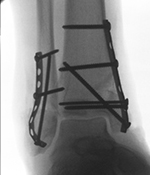

• AAOS to Launch Fracture & Trauma Registry

The Academy Registry Program will welcome a new member to its ranks when the Fracture & Trauma Registry (FTR) launches in the spring of 2021.